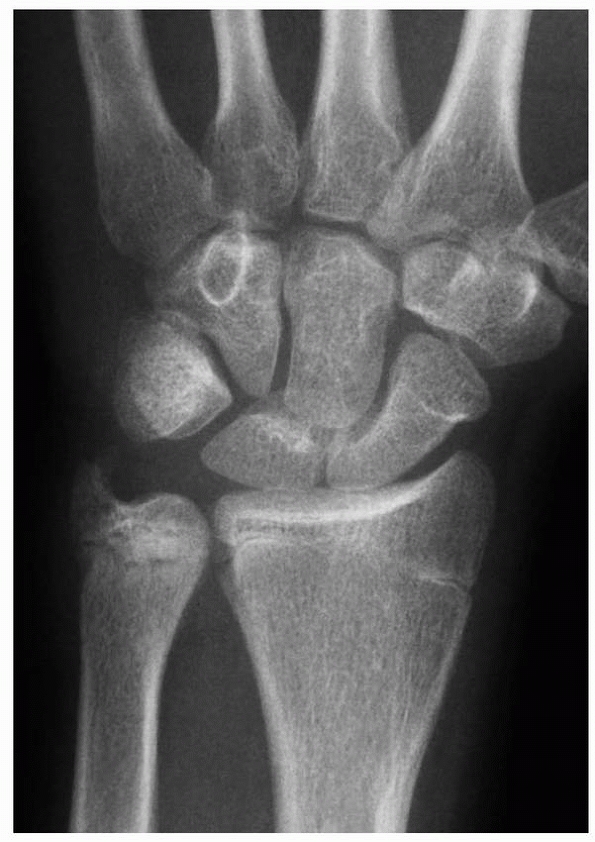

![]() |

|

FIGURE 9-24 A. AP radiograph of growth arrest with open ulnar physis. B.

MRI scan of large area of growth arrest that was not deemed resectable by mapping. Note is made of impaction of the distal ulna against the triquetrum and a secondary peripheral TFCC tear. C. Radiograph after ulnar shortening osteotomy, restoring neutral ulnar variance. |